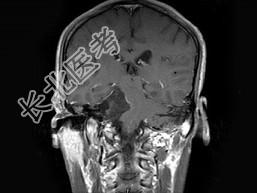

- 单项选择题男,38岁, 头痛半年余,MRI检查如图, 最可能的诊断是 ( )

A、听神经瘤

B、三叉神经瘤

C、表皮样囊肿

D、皮样囊肿

E、未见异常